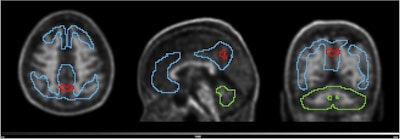

Volume with higher baseline signal for N1 accumulators and N1 non-accumulators of amyloid (red line) overlayed on the scan of an N1 accumulator (MNI space). Grey scale shows SUVR range. Blue line shows the Centiloid target region and the green line shows the reference region (whole cerebellum). Image and caption available for republishing under Creative Commons license (CC BY 4.0 DEED, Attribution 4.0 International) and courtesy of the European Journal of Nuclear Medicine and Molecular Imaging.

Volume with higher baseline signal for N1 accumulators and N1 non-accumulators of amyloid (red line) overlayed on the scan of an N1 accumulator (MNI space). Grey scale shows SUVR range. Blue line shows the Centiloid target region and the green line shows the reference region (whole cerebellum). Image and caption available for republishing under Creative Commons license (CC BY 4.0 DEED, Attribution 4.0 International) and courtesy of the European Journal of Nuclear Medicine and Molecular Imaging.

Lastlt, in a parametric image analysis of N1 accumulators, a region within the precuneus was linked to increased amyloid over time, the researchers reported.

Nonetheless, the study also validates that the precuneus is a cortical regions with early amyloid accumulation in Alzheimer’s disease and that its focal signal can lead to positive visual PET reads on images from patients with low CL values, the group added.